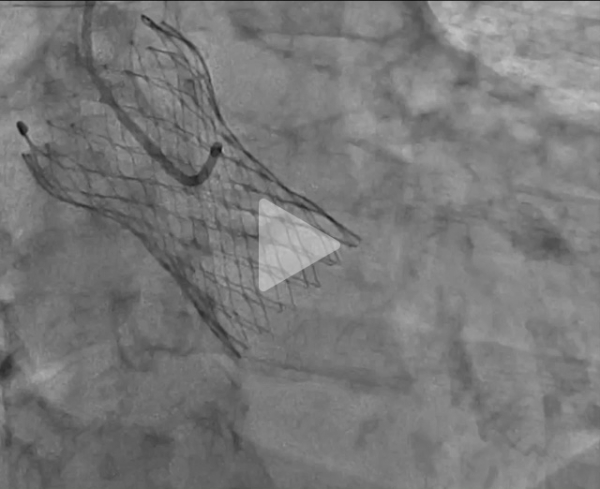

Coronarographie

Vidéo 2 : impossible d’intuber le tronc commun gauche (TCG)